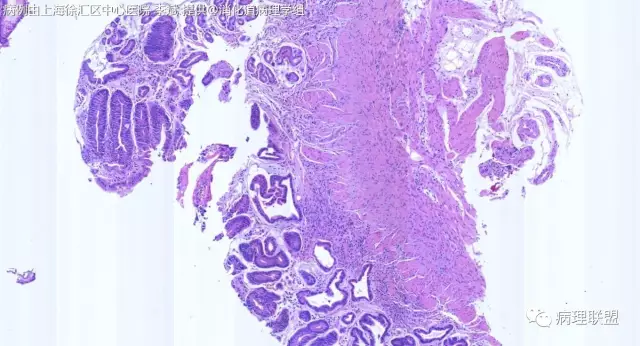

F-56 胃窦粘膜活检(低级别 vs 高级别)

女,56岁,胃窦粘膜活检(病例由上海徐汇区中心医院 李斌 提供,致谢!)

@李斌,高级别,腺体结构乱复杂,核异型性大,极向乱

@左淑英 子宫内膜受激素周期影响,腺体结构和上皮变化比较大,消化道受损伤、炎症等影响比较大,同样要看结构、看细胞,但标准确实不大一样。虽然具体病例需要具体分析,但我感觉在胃肠道,对于判断时感觉模棱两可的病例,表面成熟现象是区分反应性增生和低级别异型时可重复性相对比较好的指标;核极向是区分高低级别异型增生时可重复性相对比较好的指标。供参考